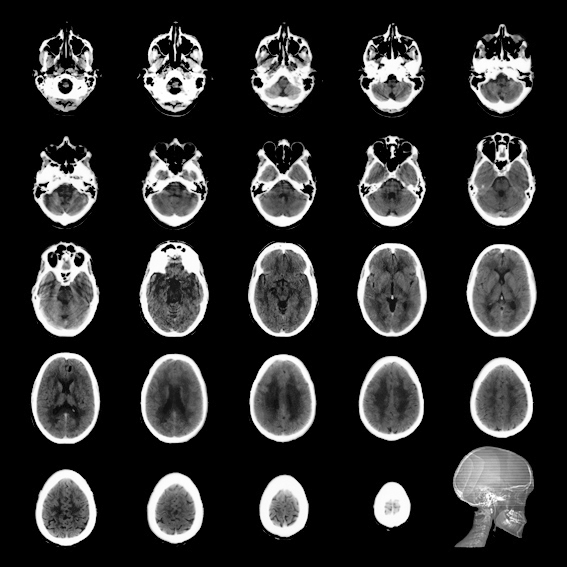

Des taches sombres et informes cernées de blanc, c’est ce qu’ont en commun l’IRM d’un crâne et des fonds de tasse à café.

Ces taches cernées ne sont apriori que des masses informes. On sait pourtant que ces taches peuvent être déchiffrées grâce aux sciences. L’une d’elles est rationnelle, l’autre est irrationnelle. Sans juger de leur véracité, ces sciences ont des buts qui peuvent être proches : comprendre l’état de santé physique ou mentale d’une personne et envisager les conséquences de cet état pour son avenir.